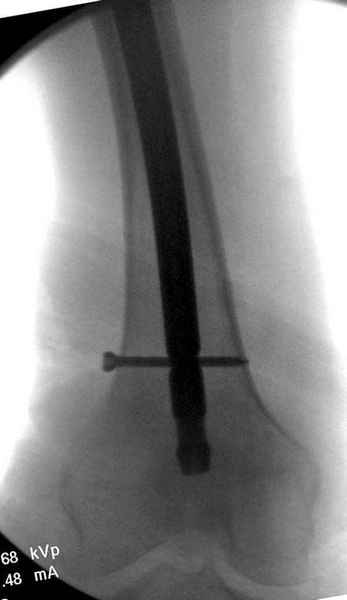

"Решайте проблемы по мере поступления. На первом этапе решение одно, и на мой взгляд верное. Ситуация изменилась кардинально - другое решение. Я бы избрал ресинтез, убрав винты заменил на Гамму. Что с ним будет послезавтра? - Будем решать послезавтра. Такая наша доля."

Правильно, ситуация изменилась, как говорят у нас теперь "different animal", надо решать проблему подвертельного перелома. При наличии различных вариантов фиксаторов, включая Страйкер Гамма 3, мы выбрали DePuy Antegrade Trachanteric Nail из-за многовариантности проксимальной фиксации и двойного изгиба. Вводится через вертел под 8 градусным углом, и есть достаточный передний диафизарный изгиб, предупреждающий пенетрацию дистального переднего кортекса.

Кто знает что дальше, мысленно готовы к проксимальной артропластике.

Решайте проблемы по мере поступления. На первом этапе решение одно, и на мой взгляд верное. Ситуация изменилась кардинально - другое решение. Я бы избрал ресинтез, убрав винты заменил на Гамму. Что с ним будет послезавтра? - Будем решать послезавтра. Такая наша доля.